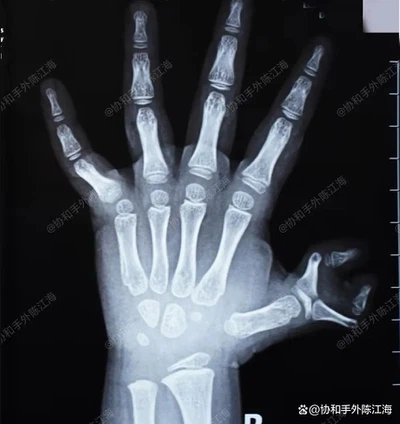

يمتلك اليد اليمنى للطفل ستة أصابع ، حيث كان كلا الإبهام منحنيًا بشدة ، مما يشكل ما يشبه مخالب السلطعون-"سلطعون المخلب المتعدد."

عندما تستخدم الفتاة الصغيرة يدها ، تتقارب الإبهامان باتجاه المركز ، مما لا يؤثر على المظهر الشديد فحسب ، بل يؤثر أيضًا بشكل كبير على الكتابة والاستيعاب. لذلك ، الجراحة المبكرة ضرورية.

الأشعة السينية قبل الجراحة